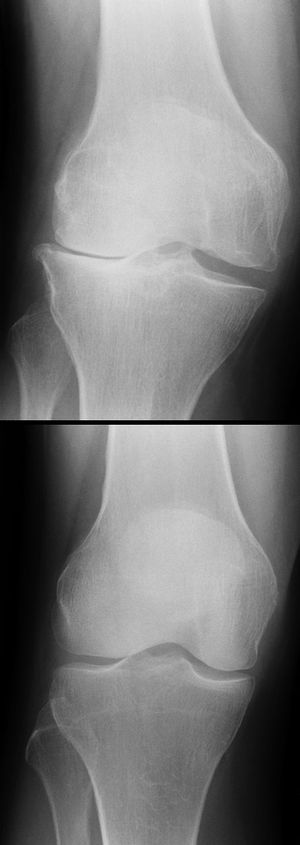

خشونة الركبة Knee osteoarthritis مرض ينتج عن تآكل الغضاريف الناعمة التي تغطي سطح المفصل والتي تساعد على نعومة الحركة. حيث يحدث ضعف في تماسك هذه الغضاريف مما يؤدي إلى تشقق سطحها ثم تتآكل تدريجياً إلى أ، يصبح سطح العظمة عارياً من الغضاريف التي تحميه. ويصاحب هذا التآكل إالتهاب في الغشاء المبطن للمفصل (الغشاء السينوفي) المسئول عن إفراز السائل الذي يساعد على تزييت سطح المفصل وهذا الإلتهاب يؤدي إلى حدوث إرتشاح (تجمع الماء) بالركبة.

من أهم أسباب خشونة الركبة تمزق الغضروف الهلالي، وتتمتع بقوة تجديدية عالية، وتجدد نفسها مع كل حركة أي أنه من كثرة تحرك المريض، يحدث تجديد لخلايا الغضاريف المفصلية.. وتستمر هذه القدرة التجديدية، لأكثر من ٥٦ عاما، ويعني ذلك أن الخشونة لا تتكون بالغضروف قبل الستين فما فوق ويستطيع الإنسان السير بدون آلام بالركبتين حتى هذه السن..

في كثير من الحالات، يشعر البعض في سن مبكرة، بالآلام في الركبتين خاصة أثناء صعود السلم، مع الشعور بطقطقة أثناء الحركة بالمفصل، مما يجعله يعتقد أنه يعاني من خشونة في الركبة، رغم قدرة الغضاريف المفصلية على التحمل والتجديد لما بعد سن الستين أو الخامسة والستين، ولتفسير ذلك يجب معرفة التركيب التشريحي لمفصل الركبة حتى يتسنى معرفة أسباب تلك الآلام في سن مبكرة.. فمفصل الركبة يمتاز عن أي مفصل آخر، بوجود الغضاريف الهلالية حيث يوجد بكل مفصل غضروفان هلاليان خارجي وداخلي علاوة على الغضاريف المفصلية المبطنة لنهايات العظام، وتكسب الغضاريف الهلالية المفصل صفة تحمل الأوزان، بالإضافة لمرونة الحركة أثناء السير، وغير ذلك من الحركات اليومية، إذا حدث تمزق بأي جزء من أجزاء هذا الغضروف الهلالي، فإنه يسبب ألما بالركبة أثناء السير، مع الشعور بطقطقة أثناء الحركة، مما يوحي للمريض أنه يعاني من خشونة بالركبة، ويزيد من هذا الاعتقاد عدم قدرة المريض على جلوس القرفصاء أو ثني مفصل الركبة كاملا، وهو ما يحدث للاعبي كرة القدم، وغيرها من الألعاب الرياضية حيث تلتوي الركبة أثناء مزاولة الرياضة، فيتمزق ذلك الغضروف ..